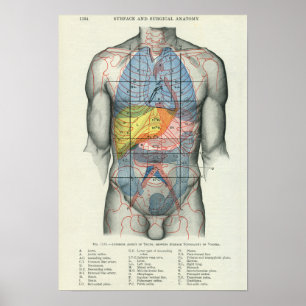

Carta do poster da anatomia do órgão interno do

Preço56,50 €

Impressão humano da anatomia dos órgãos interno

Preço15,60 €